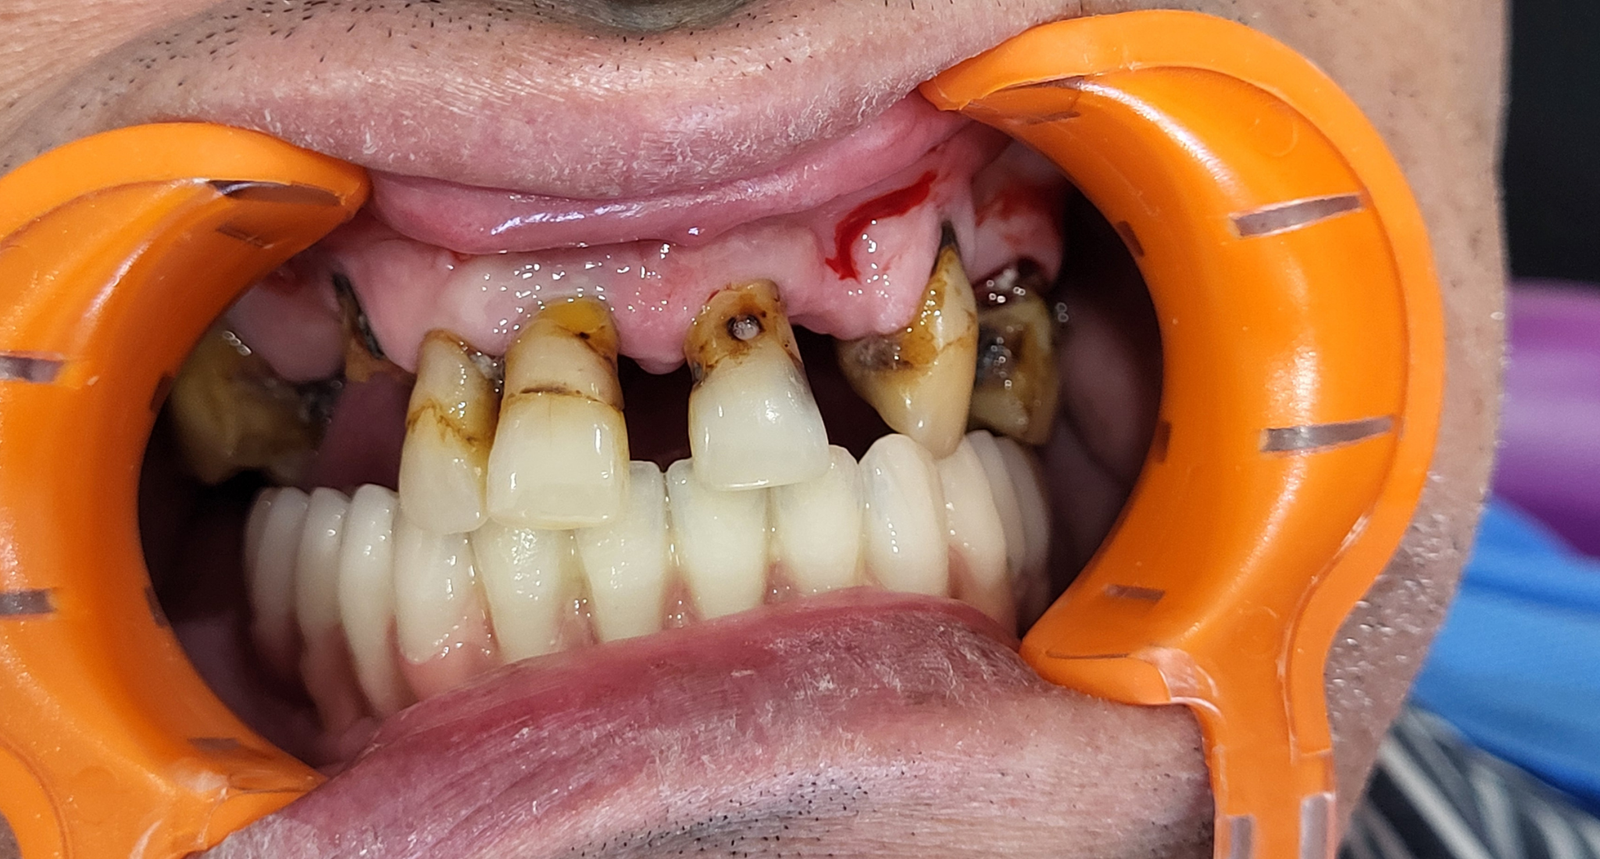

Réhabilitation complète avec mise en charge immédiate (4 implants bas / 6 implants haut)

Le patient se présente avec des dents qui bougent, en haut et en bas.

Nous avons commencé par la mâchoire inférieure avec 4 implants et une mise en charge immédiate.

Trois mois après, le haut a été fait avec le même principe avec 6 implants.

Cette fois-ci, il existait un déficit osseux, résolu par une technique d’expansion sans avoir recours à la greffe d’os.

Les prothèses réalisées sont vissées, ce qui permet de les enlever, les nettoyer une fois par an, ou résoudre n’importe quel problème.